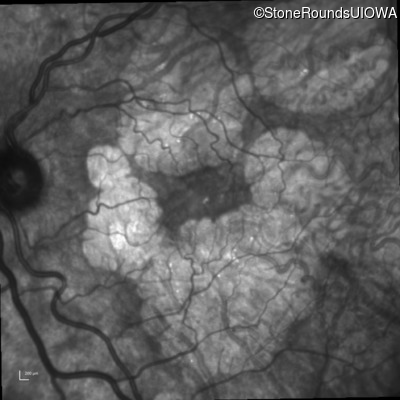

Infrared Fundus Photograph - Right - 20/40 -2

Exemplar